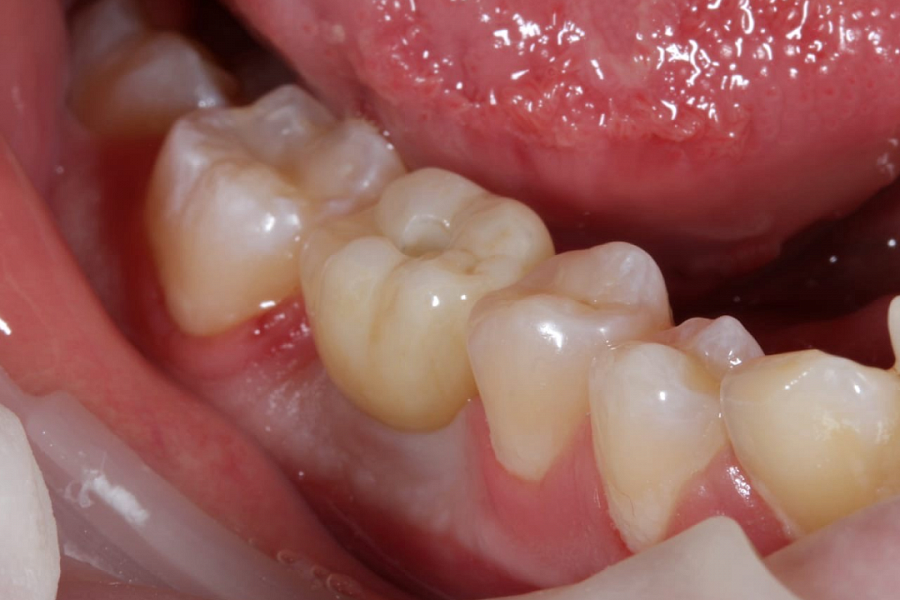

Пациент направлен врачом-терапевтом для удаления зуба 46 (нижний шестой зуб справа) и одновременной постановки имплантата.

Зуб был фрагментирован, чтобы удаление прошло максимально атравматично, то есть без повреждения окружающих костных стенок. После удаления установлен имплантат. Операция прошла успешно, пациенту уже установлена зубная коронка.